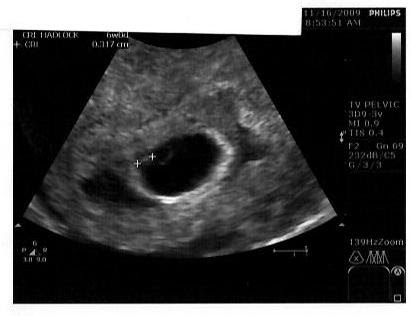

However, some women do need a scan before 12 weeks . Between 8 - 12 weeks of pregnancy is a good time for a dating scan . A 2-D image of a baby at about 8-9 weeks . Small arms are becoming visible, sticking out slightly in the middle of the baby . The wavy line near the bottom of the image measures the heartbeat which in this baby is

If you're not sure when you conceived, or, have had a previous miscarriage or pregnancy complications, an 8 - 10 week scan may be recommended . There's a lot which can be seen at 8 weeks gestation, including the baby's heartbeat and early development . It will also be possible to work out the baby's due date, which is why an 8 week ultrasound is often called a dating scan .

A dating scan is the most accurate way to predict your due date, also known as your estimated date of delivery (EDD) . The point of the scan is to work out how many weeks pregnant you are . You may have calculated the length of your pregnancy from the first day of your last menstrual period (LMP) .

The primary purpose of this scan is to confirm pregnancy dating and determine health . The scans will last about 10 minutes and a 2D scan picture will be given to you to take home and keep . All early scans are performed by a qualified diagnostic Sonographer . As this package is offered from 6 weeks , it is medically recommended that the scan is . . .

A dating scan is usually done to check how many weeks' pregnant you are, but can be done for other reasons, such as if you have had bleeding during your pregnancy or you have had previous miscarriages . If you choose to have a dating scan , it will most probably be your first scan . You will need to get a referral from your doctor or midwife for . . .

If you're pregnant in England you'll be offered an ultrasound scan at around 10 to 14 weeks of pregnancy . This is called the dating scan . It's used to see how far along in your pregnancy you are and check your baby's development . The scan may also be part of a screening test for Down's syndrome . Your midwife or doctor will book you a dating scan appointment . It will usually take place at your local hospital ultrasound department .